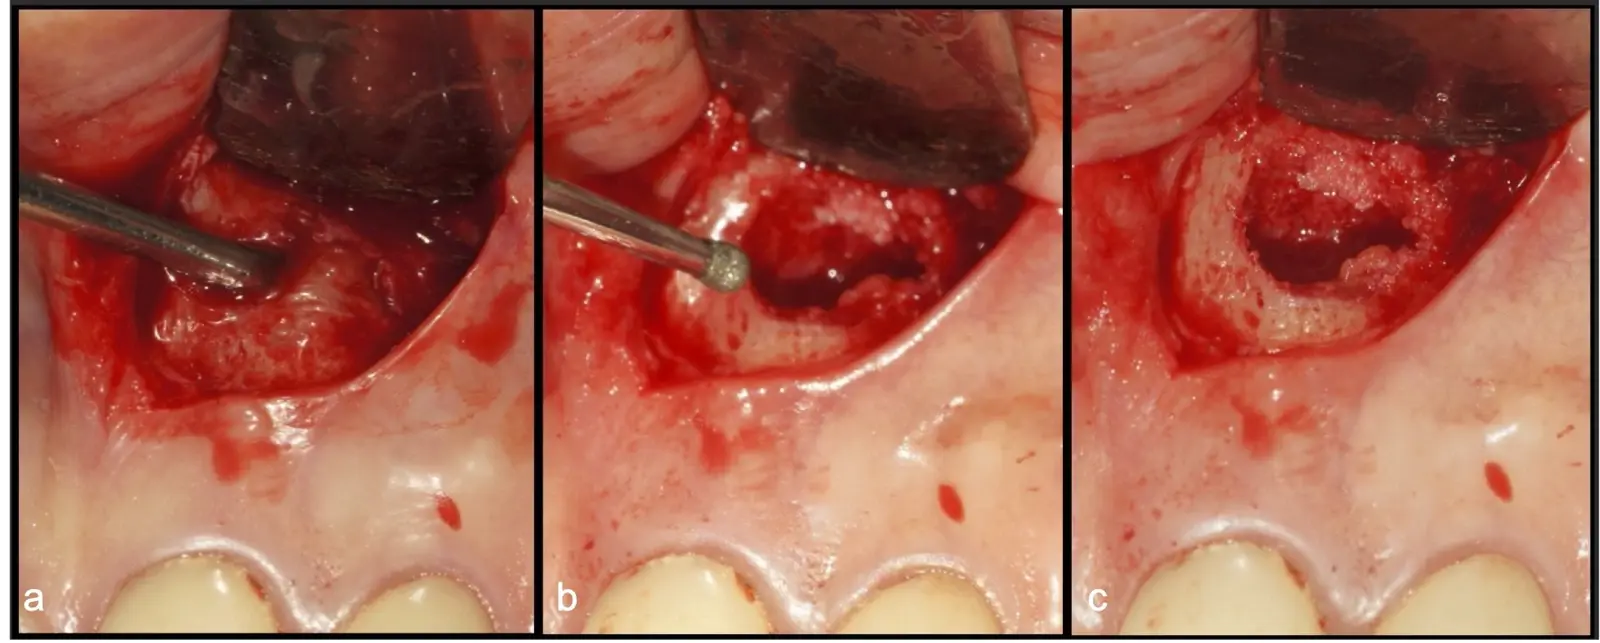

Después de realizado el acceso e identificado el ápice, se procede a la limpieza de la zona con instrumentos manuales y/o con insertos diamantados de parte activa angulada para poder eliminar todo el tejido patológico del perímetro radicular apical y del tejido óseo circundante (Figura 6).

Una vez limpia la zona apical, se corrobora la integridad de la raíz y se evalúa el grado de extensión de la lesión. Si el defecto óseo es pequeño, se procede a realizar la preparación del conducto y obturación retrógrada de ser el caso. Si el defecto óseo es de gran tamaño e inaccesible a los insertos, se procede a realizar un corte de por lo menos 3 mm de ápice radicular conteniendo los posibles conductos aún infectados11 empleando habitualmente insertos de borde aserrado con/sin marcas de medición para un trabajo seguro7 (Figura 7).

Aunque algunos autores recomiendan evitar los ángulos en bisel para no exponer excesivamente túbulos dentinarios por riesgo de una posterior microfiltración18, en la cirugía apical piezoeléctrica recomendamos realizar un bisel externo para tener un mejor acceso al ápice. La configuración de los insertos de piezoeléctrico permiten realizar un corte lo más cercano a los 0°-10° de bisel11 con acceso adecuado a la zona de posterior obturación (Figura 8).